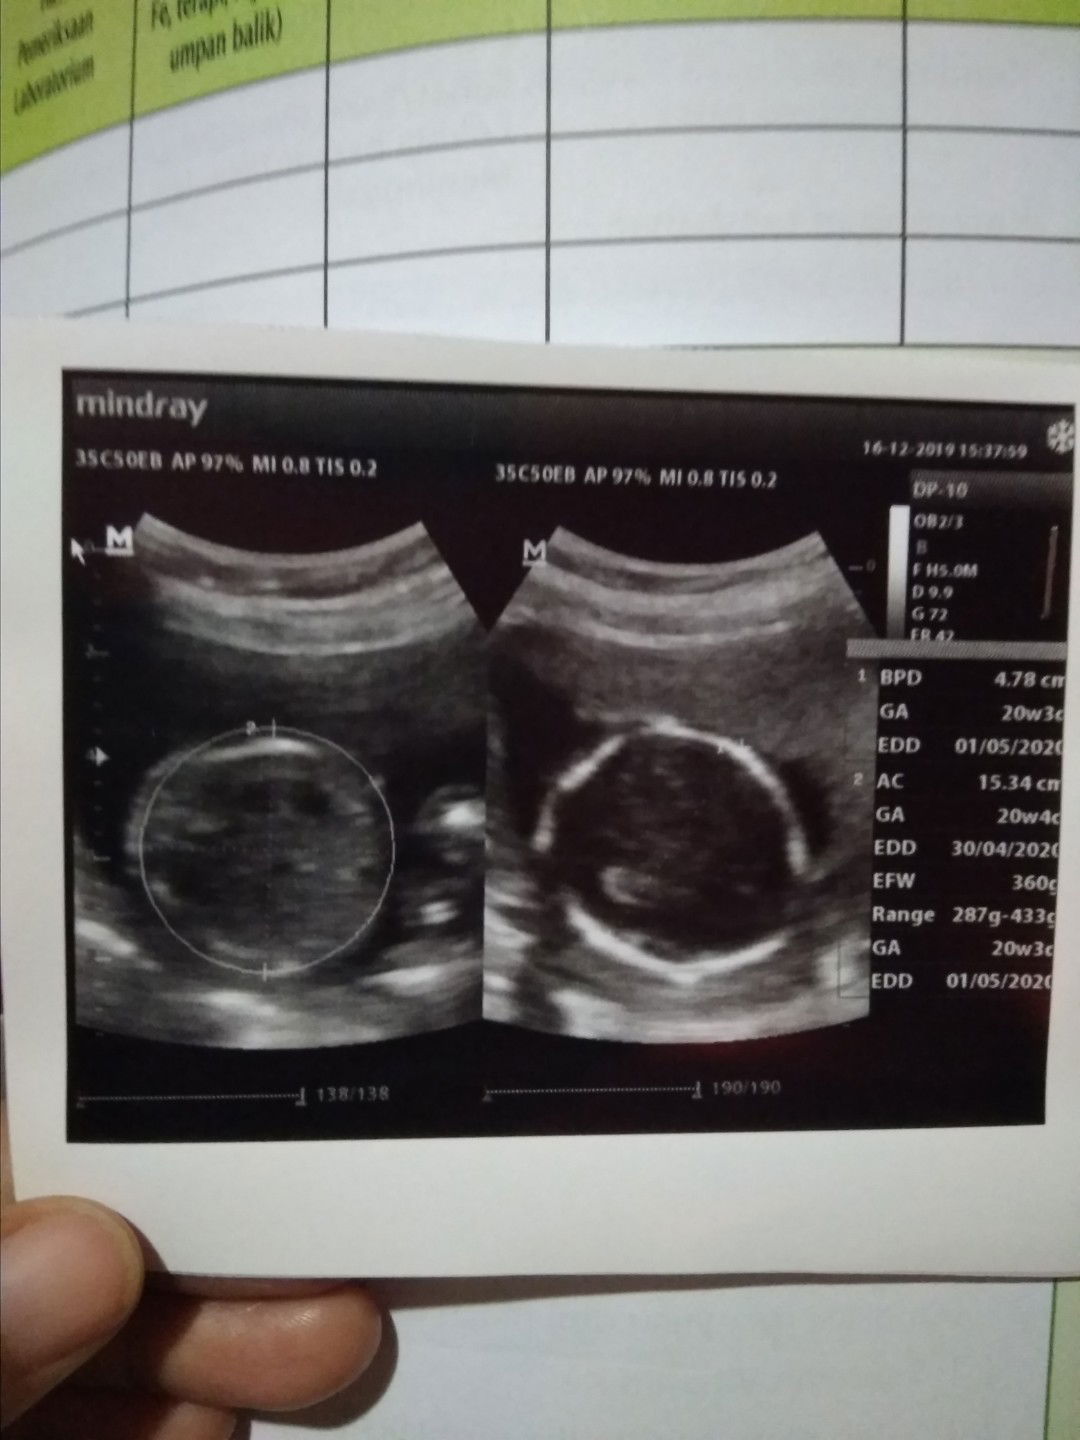

Hasil USG

Alhamdulillah hasil usg kemaren semuanya baik sehat dan kumplit?,walau belom kelihatan jenia klaminnya gpp yang penting dedek di baik2 aja ?. Semangat naikin HBnya dedek karna HBnya kurang ??